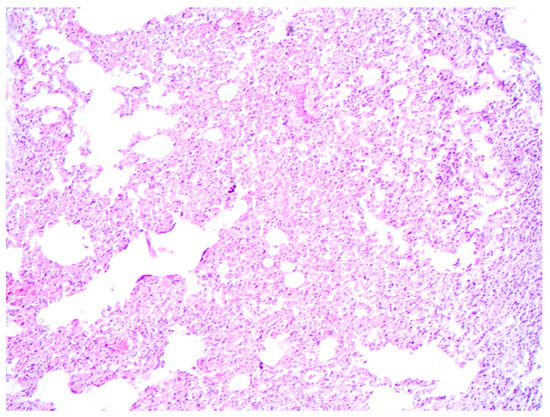

Microscopically, pulmonary atelectasis was observed (Figure 2) and changes in the architecture of the lymph nodes were observed, resulting from a marked cellular infiltrate composed of lymphocytes and histiocytes, associated with macrophages with intracytoplasmic Leishmania amastigotes and neutrophils (Figure 3A,B), as well as areas of hemorrhage and necrosis. The bone marrow showed inflammatory infiltrate composed of foamy macrophages, plasma cells. Leishmania amastigotes were found in the cytoplasm of macrophages. Microscopic evaluation of the skin revealed marked diffuse inflammatory infiltrate of lymphocytes, plasma cells, and macrophages with intracytoplasmic structures compatible with Leishmania amastigotes.

Figure 2. Canine Leishmaniosis associated with acute aleural effusion and sudden death in a dog. Pulmonary atelectasis characterized by collapsed alveoli, where the alveolar spaces are notably compressed. Hematoxylin and eosin. Obj. 10×.